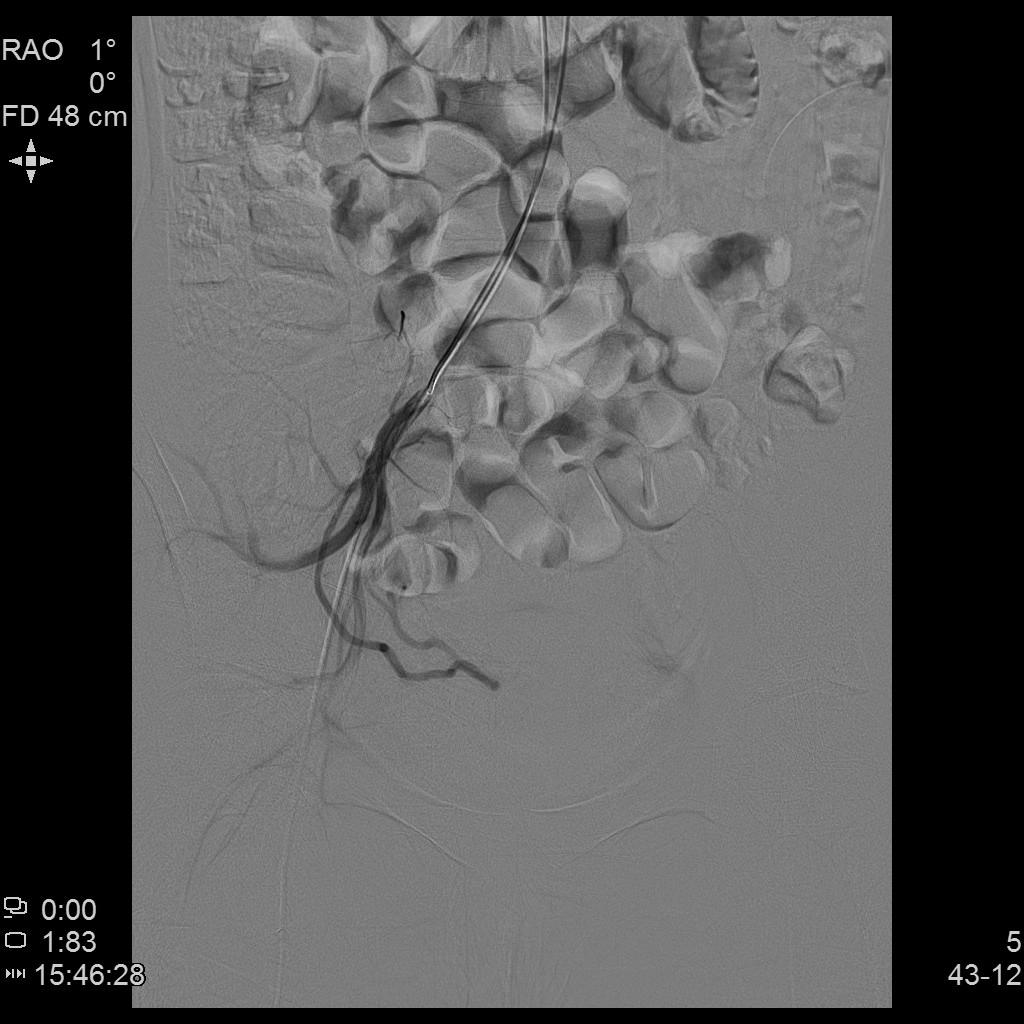

例2

中年患者,患有“子宫腺肌瘤”7年余,长期受痛经、月经量增多折磨,严重影响生活质量。经多处求医,经历药物调理、“曼月乐”宫腔植入、“海扶刀”消融术等多种治疗,痛经、月经量多等情况一直无法得到有效缓解,病情日益严重。

- 术前MRI检查显示子宫明显增大。

术前MRI检查显示子宫明显增大

- 插管至右侧子宫动脉,显示子宫右侧病灶情况

右侧子宫动脉造影